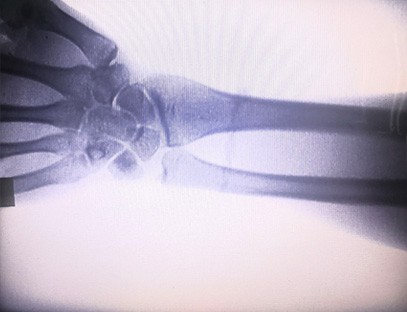

Specializace:Určeno pro potřeby ortopedických klinik, vhodné zejména prorentgenové zobrazováníkončetin, jako jsou ruce, zápěstí, lokty, ramena, kolena, kotníky atd.

Jasné zobrazení:K poskytování vysoce kvalitních rentgenových snímků se používá pokročilá digitální zobrazovací technologie, která lékařům pomáhá přesně diagnostikovat stav.